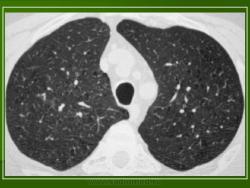

В 5 наблюдениях (21%) из больных с распространенной формой заболевания отмечались изменения в легких в виде обогащения, избыточности легочного рисунка, его деформации по сетчато-петлистому типу, очаговых теней. Корневая и медиастинальная аденопатия отсутствовали. В 1 случае в легких выявлена киста, которая периодически осложнялась нагноением (Рис. 4).

Поражение легочной ткани (рис. 22) свойственно любому возрасту. Часто больные имеют общие симптомы — лихорадку, слабость, реже — кашель, одышку, боли в грудной клетке. На рентгенограммах отмечается деформация и усиление легочного рисунка и микроузловые инфильтративные тени. Поражение костного мозга (с наличием клеток Лангерганса) сопровождается цитопенией периферической крови.

Рис. 22. Поражение легких при Лангер-гансово-клеточном гистиоцитозе.